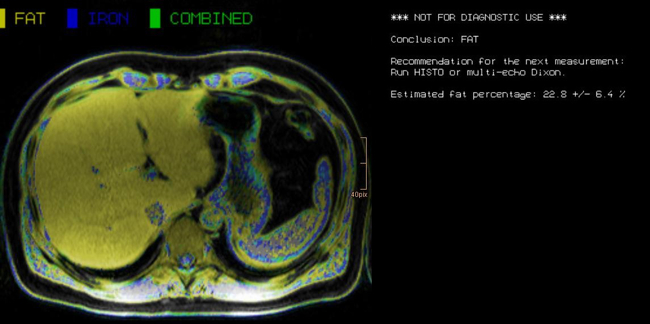

Abdominal MR Imaging

Michaela Plaikner, Benjamin Henninger, Christian Kremser

Morphological and functional MRI in all-organ systems development of novel MRI applications and MR sequences. Examples of research projects: fat, iron or combined disease; influence of iron on the evaluation of liver fat.

a) MRI for the evaluation of diffuse liver disease:

evaluation of different MRI methods (relaxometry, chemical shift imaging, multi-echo approach, Dixon screening), in order to detect diffuse liver disease (fat, iron or combined disease); influence of iron on the evaluation of liver fat.